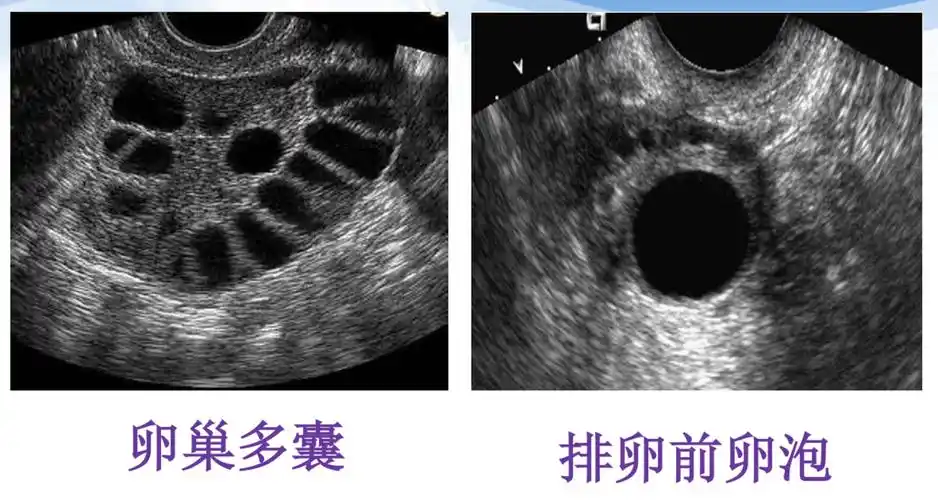

为什么要监测卵泡